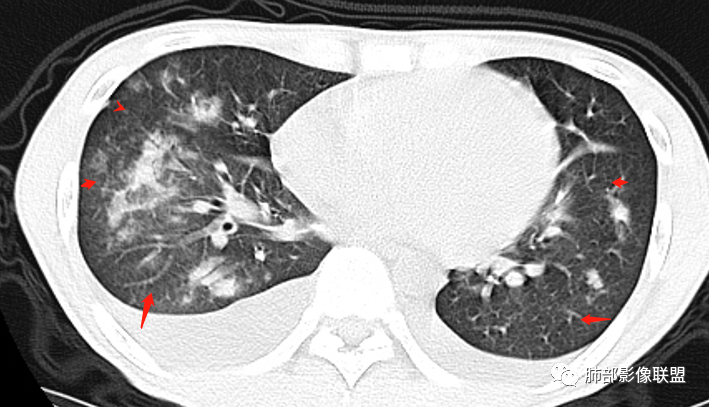

ggo完全消失抗感染治疗2周后,复查ct提示结节消失ct提示左肺上叶磨

抗感染治疗2周后,随访1个半月,混合型ggo明显吸收4.

双下肺淡薄ggo